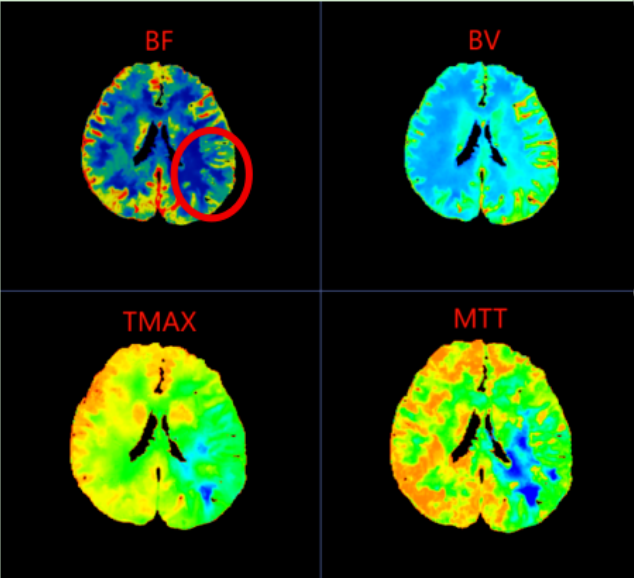

在一脉阳光辽宁影像中心,44岁的李女士(化名)带着持续了40余天的头晕与头痛,完成了一次看似平常却至关重要的检查——脑灌注CTP扫描。图像清晰显示:她左侧大脑中动脉供血区存在明显的低灌注区域,平均通过时间显著延长,脑血流量下降。

诊断结果明确:脑梗死前期I2期改变。这意味着,她的脑血流自我调节机制已开始失代偿,脑组织正处于缺血危机边缘,但梗死尚未真正发生——这是身体发出的最后预警。

李女士的CTP图像中,左侧大脑中动脉供血区呈现的“低灌注”表现,正是脑血流代偿机制开始崩溃的标志。这种梗死前的影像预警,为临床实施超早期干预——如强化抗血小板治疗、控制血压、改善脑灌注等——提供了至关重要的依据,从而有可能阻断病情进展,避免梗死发生。